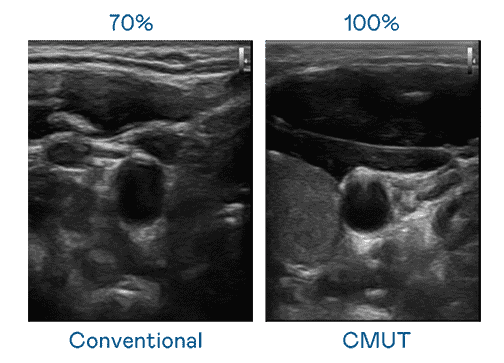

CMUT 技术是一种用电容式微机电元件来产生超音波讯号的技术。。。。与传统 PZT 压电式技术相比,,CMUT 频宽增加 30%,,,,更宽频的超音波讯号让影像解析度大幅提升,,是实现高影像品质医疗超音波扫描、、、、促进精准医疗发展的关键技术。。。

超音波影像的解析度高低,,首先取决于探头能发出的讯号频宽。。。红龙扑克 CMUT 可提供高清晰的超音波讯号,,提供高频宽、、高灵敏度、、影像纹理细节更高的超音波影像,,,协助医护人员缩短影像判读时间及利用精准的医疗影像进行诊断。。